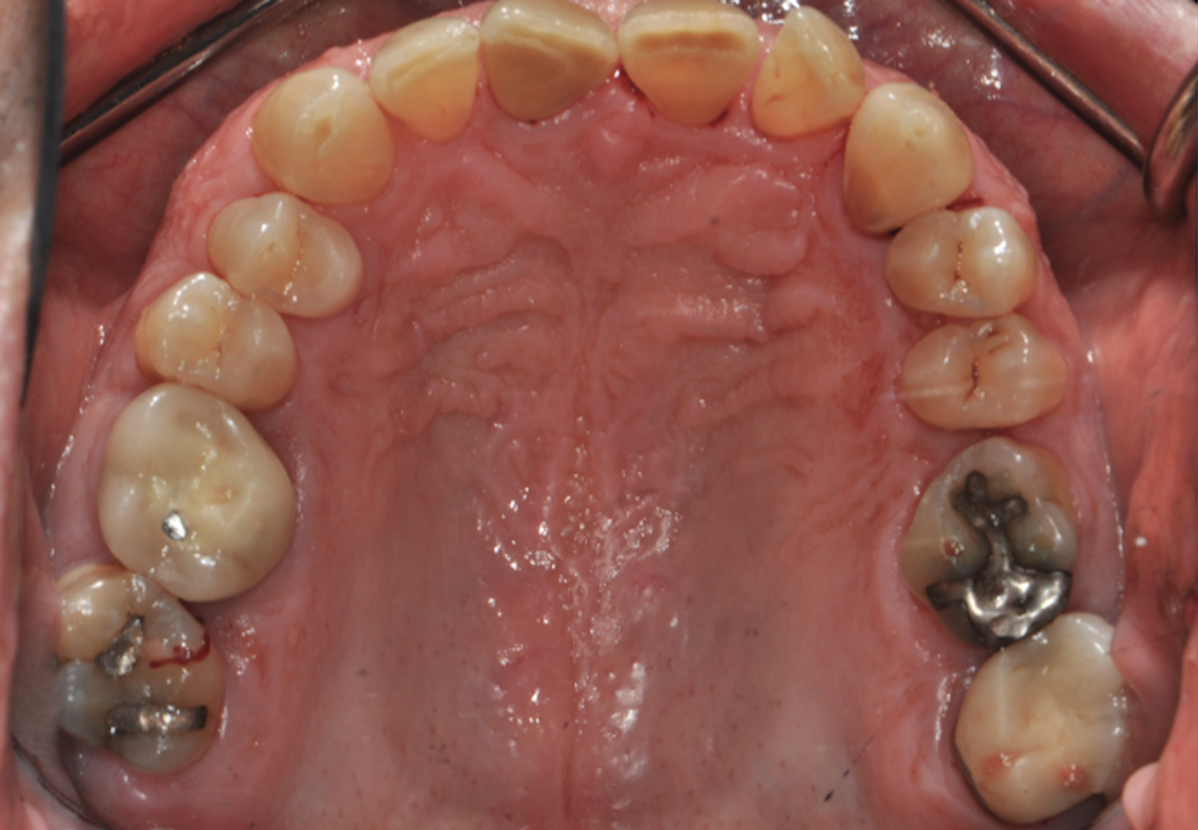

Fig 5. Pretreatment occlusal views: maxilla (Fig 5) and mandible (Fig 6).

Figure 5

Periodontal examination revealed generalized BOP and PDs up to 9 mm in the maxillary and mandibular molars with multiple furcations in each molar (Figure 2 through Figure 7). He presented with class I mobility in many posterior teeth and class II mobility in teeth Nos. 3 and 9 (maxillary right first molar and maxillary left central incisor, respectively). The periodontist decided to score tooth No. 3 for the PRS, as this was the most periodontally involved molar that was planned to be treated and maintained (Figure 2 and Figure 8). This tooth (maxillary right first molar = score 1) presented with probing depths of 7 mm (score 1); three total furcation invasions (score 3) (mesial [degree II furcation], buccal [degree I furcation], and distal [degree II furcation]); and a class II mobility (score 2). The total PRS for tooth No. 3 was 8, representing a "guarded" prognosis. Based on this score, the likelihood of not losing any teeth to periodontal disease for 15 years was 81%, and for 30 years the likelihood was just 56% (Figure 9).7